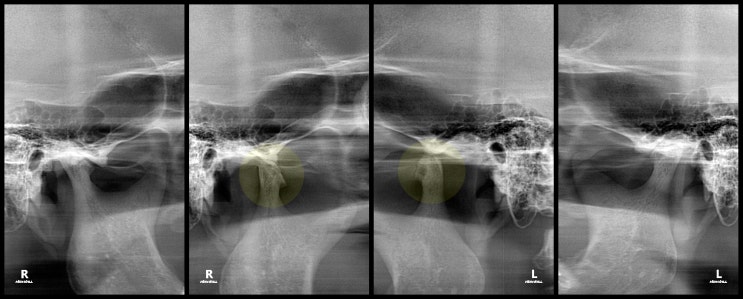

항상 볼쪽이 조이는 느낌이 들고,

1주일 전부터 왼쪽 턱이 아파요.